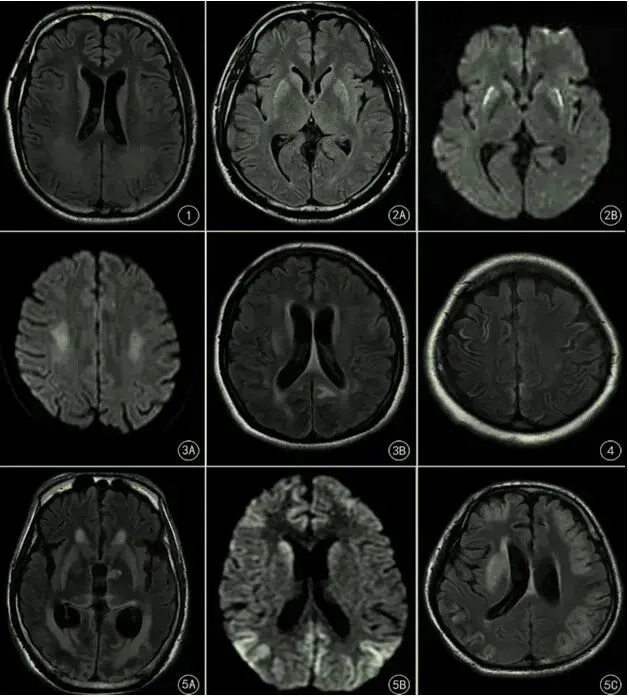

脑室周围白质损伤型

[1] 男,38岁电击伤致心跳呼吸骤停行心肺复苏成功后,FLAIR示双侧侧脑室旁白质异常高信号。

深部灰质损伤型

[2A,2B] 女,25岁,一氧化碳中毒致心跳呼吸骤停行心肺复苏成功后FLAIR(A)DWI(B)示双侧尾状核和苍白球呈异常高信号。

分水岭型

[3A] 男,40岁,急性脑梗死,突发心脏呼吸骤停行心肺复苏成功后,DWI示大脑半卵圆中心和放射冠区深部白质(内侧分水岭)高信号。

[3B] 女,31岁,宫外孕术中突发心脏呼吸骤停。FLAIR示枕叶(皮层分水岭)斑片状高信号。

中央沟周围皮质损伤型

[4] 女,45岁,剖宫产术后突发心跳呼吸停行心肺复苏成功后,FLAIR示中央沟周围皮质高信号。

混合损伤型

[5A] 男,43岁,无诱因突发心脏呼吸骤停行心肺复苏成功后,FLAIR示双侧基底节、双侧丘脑、双侧后皮层分水岭高信号。

[5B] 女,45岁,剖宫术后心跳呼吸骤停经心肺复苏术后,DWI示双侧尾状核、分水岭高信号。

[5C] 男,25岁,药物中毒导致呼吸衰竭引起心跳呼吸骤停,FLAIR示双多基底节区、大脑皮质高信号。